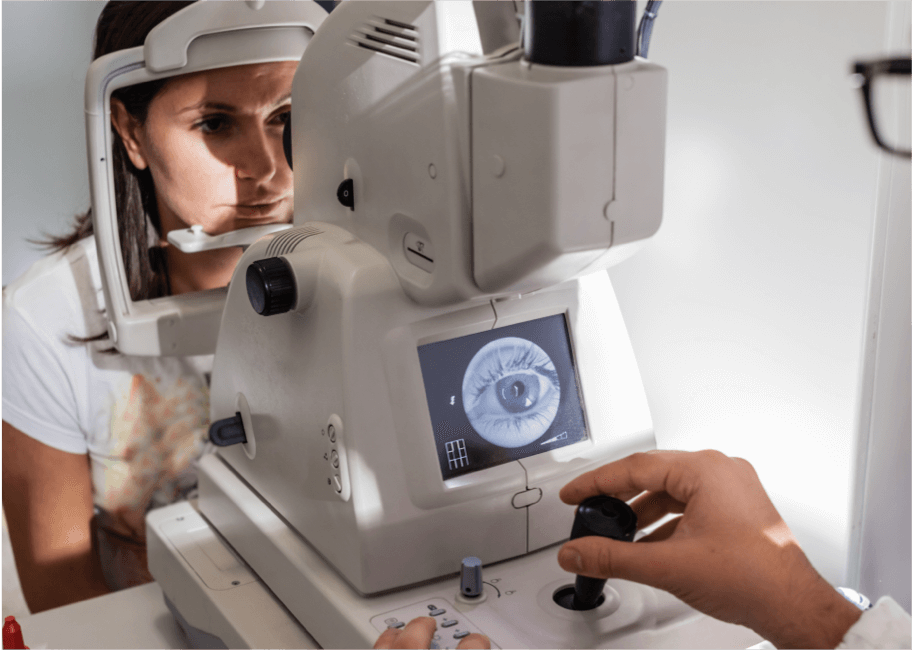

Oftalmoscopia com lâmpada de fenda

Este método é bastante usado para diagnosticar a DMRI. Com o queixo apoiado no aparelho de lâmpada de fenda, uma luz em fenda estreita é direcionada ao olho do paciente, permitindo o exame do fundo de olho com uma lente de aumento.6